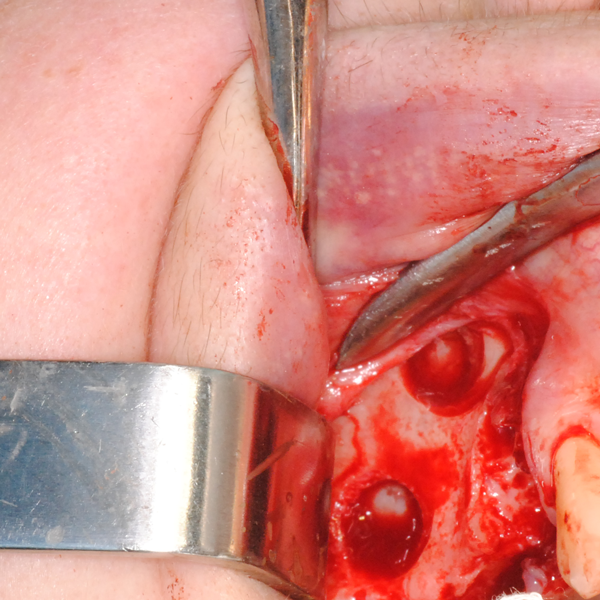

Отворен максиларен синус в началото на интервенцията. Случаят е интересен със следното - твърде атипична форма на трепанационния отвор. На какво се дължи на това - на лошо планиране на оперативния достъп или на нещо друго? Дължи се на факта, че отначало въпросната намеса беше планирана като балонен синуслифт; за съжаление обаче мембраната на синуса се разкъса и надуването на балона стана невъзможно.